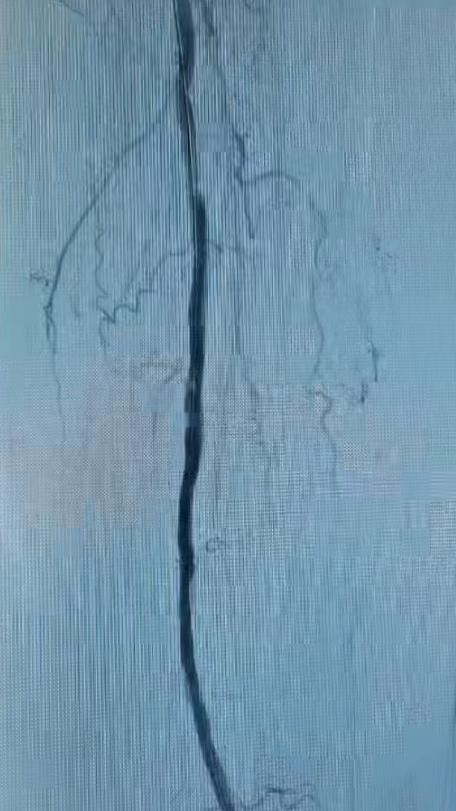

术前(左)、术后(右)小腿动脉的IVUS对比

在激光成功“开路”后,团队再辅以必要的球囊扩张,最终实现血管的完美重建。术后复查显示,患者下肢血流恢复通畅、疼痛消失,保肢成功,生活质量得到根本性改善。